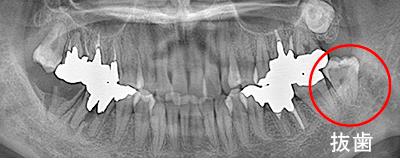

抜歯した親知らずを移植(1)

Before

After

左上の親知らずの歯を移植しました。20代前半の症例です。

ご自身の歯のため親和性が高く、移植後も不自由なく機能しています。